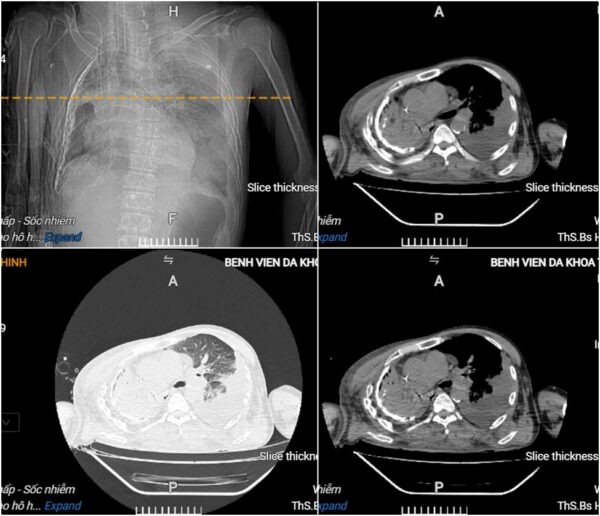

Kết quả xét nghiệm cho thấy người bệnh bị toan chuyển hóa, suy đa tạng, nhiễm trùng – nhiễm độc nặng, rối loạn đông máu. Hình ảnh chụp cắt lớp vi tính lồng ngực ghi nhận ổ áp-xe phổi trái kích thước lớn kèm theo tràn dịch màng phổi phải.

Hình ảnh cắt lớp vi tính lồng ngực của người bệnh cho thấy có áp-xe phổi trái lớn, tràn dịch màng phổi phải